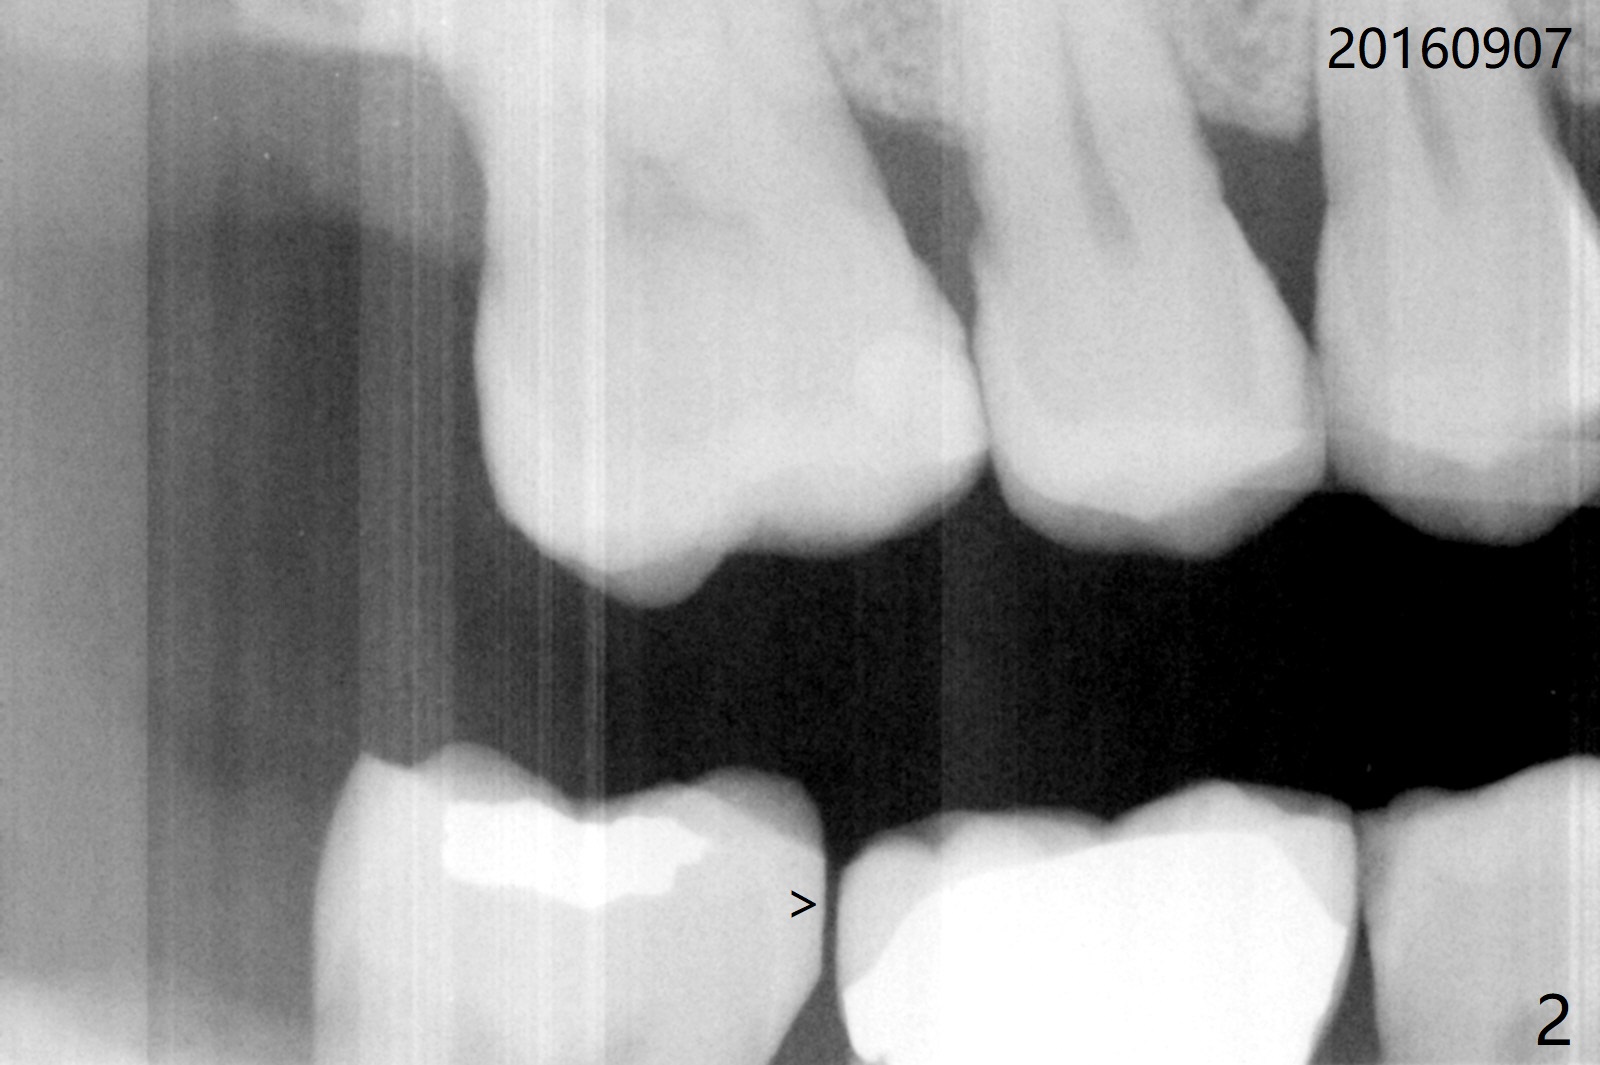

A 71-year-old man finally agrees to have an implant to be placed at #2 four years being our patient. The break point is that the crown at #30 needs recementation. The tooth #2 was missing when he presented for new patient exam (Fig.1,2). The bone loss between #30 and 31 is mild (Fig.1 *) with a small diastema (Fig.2 >). Porcelain chips at the pontic (Fig.3 >). The bone height at #2 is limited (Fig.4). The bone loss and the diastema seem to have got worse in the last 3-4 years (Fig.5). The tooth #15 has mobility with exposure of the buccal roots (Fig.6). Because of bruxism, consider flap surgery to bury the implant at #2 with guide.